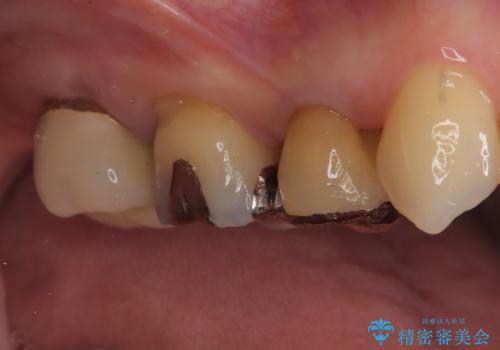

- 古い被せ物をやり変えたいことを主訴に来院されました。

根管治療も行い、きれいな被せ物になり患者さんも喜んでいました。

3本まとめて治療をすることで来院回数を減らし、患者さんの負担を減らすことができ喜んでいただけました。